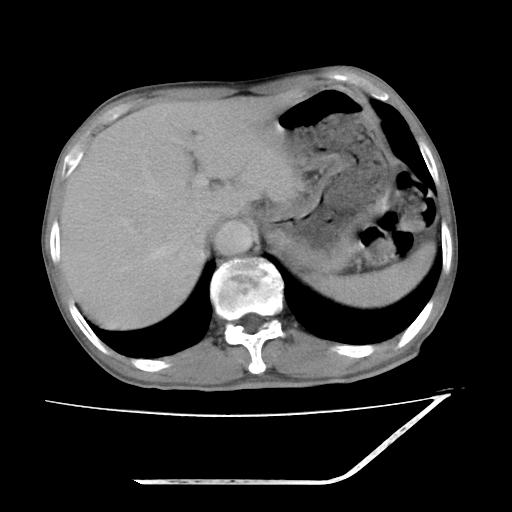

增强

考虑右肾盂癌,肾动脉受侵,右肾功能减退,右肾盂输尿管积水,管壁增厚,考虑种植转移,应该把下面扫完的

支持右侧肾盂癌伴肾静脉瘤栓形成可能性大,右肾结石.肝右叶后段低密度影,不除外转移.

考虑右肾盂癌,肾动脉受侵,右肾功能减退,右肾盂输尿管积水,管壁增厚,考虑种植转移  支持

右肾盂旁ca并肾静脉瘤栓形成/肾功能降低。

右肾结石。

右肾盂癌,肾动脉受侵,右肾盂输尿管积水,管壁增厚,考虑种植转移

右肾盂移行细胞癌并右输尿管中段转移.肾积水.

支持 右侧肾盂癌伴肾静脉瘤栓形成可能性大,右肾结石;肝右叶后段低密度影,不除外转移。

1.右侧肾盂癌伴肾盂积水。

2.肾脏功能减退,原因有:(1)肾动脉受侵。(2)肾静脉受侵(3)肾积水,等。本例,肾动脉显影较好,但受压明显;肾静脉无明显显示,受压或静脉癌栓,下腔静脉腔内未见明显充盈缺损。

3.右侧上段输尿管扩张,原因:(1)积水所致;(2)种植。